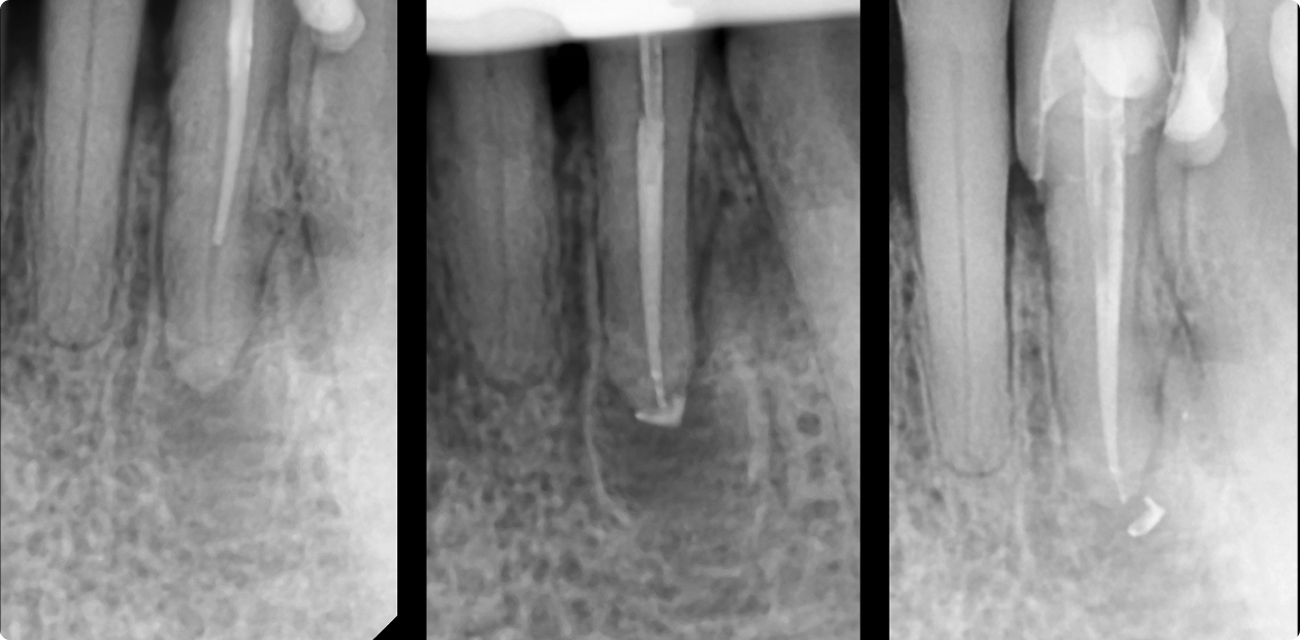

La endodoncia realizada en nuestra clínica dental de Castellón por el dr Francisco Monzó Es la rama de la odontología que trata la patología de la pulpa ( nervio) y de los tejidos alrededor de la raíz. Se ocupa de prevenir las infecciones dentales, de su curación y de regenerar el propio hueso perdido alrededor del diente como consecuencia de la enfermedad del diente.

El tratamiento se basa en una fase de limpieza del diente, tanto a nivel de su corona como de sus raíces. Una vez limpio se procede a rellenar tanto los conductos de las raíces como la corona del diente. Hoy en día tenemos la suerte de contar con sistemas de obturación que nos permiten poder rellenar en espacios que antes no podíamos. De esta manera nos aseguramos un tanto por ciento mayor de éxito en nuestros tratamientos.

La endodoncia es una práctica fundamental en nuestra clínica de Castellón. Nuestro lema es “ como tu diente no hay nada”. Creemos firmemente en ella como medio para conservar/ salvar los dientes durante mucho tiempo. Para ello nos ayudamos de la última tecnología, ya sea mediante el microscopio o el CBCT ( radiología 3D). Gracias a ellos podemos ver donde antes no veíamos. De esta manera aumentamos la calidad del tratamiento y disminuimos tiempos.

Las Radiografías digitales son una clase de radiografías que utiliza un pequeño sensor en lugar de la placa radiográfica convencional. El sensor transmite la imagen al monitor de una computadora y puede ser vista en la pantalla tanto por el profesional como por el paciente.